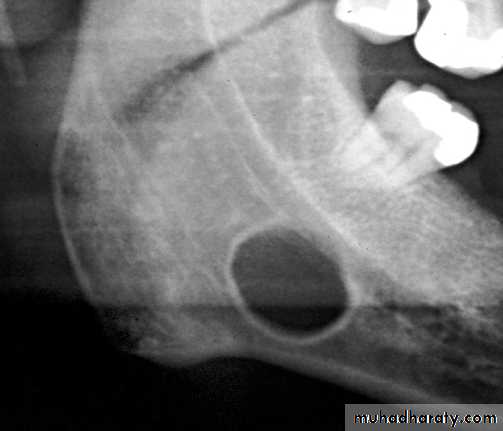

A well-defined lesion is one in which most of the periphery is well defined. If an imaginary pencil can be used to draw confidently the limits of the lesion, the margin is well defined.

Ill-defined periphery difficult to draw an exact delineation around most of lesion.

Well-Defined Borders

1-Punched-Out Border. A punched-out border is one that has a sharp boundary there is no bone reaction apparent immediately adjacent to the abnormality.2-Corticated Border. A corticated margin is a thin, fairly uniform radiopaque line of reactive bone at the periphery of a lesion. This is commonly seen with cysts and benign slow-growing tumors

3-Sclerotic Margin. A sclerotic margin made up of a thick radiopaque border of reactive bone that usually is not uniform in width. This margin may be seen with periapical osseous dysplasia and may indicate a very slow rate of growth or the potential for the lesion to stimulate the production of surrounding bone